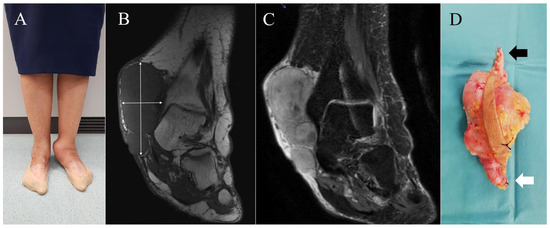

Figure 3.

Case 6. (A) = Clinical appearance of a woman with a large tumor on the inner aspect of her left ankle. (B,C) = Coronal T1-weighted and coronal T2-weighted, fat-suppressed MR images exhibit a giant subcutaneous lobulated nonspecific mass (blue arrows). In this case, continuity with vascular structures was not established, probably due to its large size. The lesion is in contact with tibial epiphysis, but no associated osseous changes were demonstrated. (D) = Specimen with marginal margin of resection. The skin island that includes the biopsy tract is identified; the ends of the great saphenous vein are indicated: proximal end (black arrow) and distal end (white arrow).